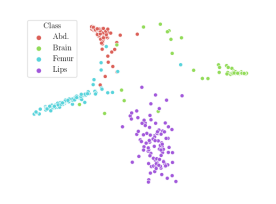

We compare the -distance of categorical features and domain features. Fig. 5 (a) shows that domain difference is higher in domain features than in categorical features. This indicates that domain features contain more domain information whereas categorical features are more domain-invariant. Fig. 6 shows the t-SNE plot of categorical features in both domains for MIDNet. From Fig. 6 (a), we observe that the categorical features learned by MIDNet enable the anatomical classification. Fig. 6 (b) shows that the learned categorical features are domain-invariant.

In addition, we utilize t-SNE plots for feature visualization in Fig. 10. Comparing Fig. 10 (a) and Fig. 10 (b), we observe that with mutual information disentanglement, (1) samples from the same category are more tightly clustered (see the top row) and (2) the source domain and the target domain are overlap more (see the bottom row). This indicates that mutual information disentanglement is important for learning categorical-focused and domain-invariant features. Fig. 10 (a), (c)-(d) show that the proposed method outperforms other state-of-the-art methods for learning category-discriminative and domain-invariant features, especially for unseen categories in the target domain (e.g., (a) vs. (d)).